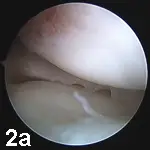

Stifle JointIn our practices, the stifle is the most commonly "scoped" joint. Typical indications include diagnosis and treatment of cruciate ligament disease (Figure 1), meniscal injury  (Figures 2A and B), and osteochondritis dissecans (OCD). Arthroscopy provides magnification, access, and fluid distention, allowing a more thorough evaluation of the stifle joint than with

arthrotomy. Damaged cranial cruciate ligaments can be accurately debrided with small power-driven shavers. Meniscal tears can be identified and treated with partial meniscectomy or, in some cases, repaired OCD lesions can be debrided and autogenous osteochondral grafts placed via arthroscopy.